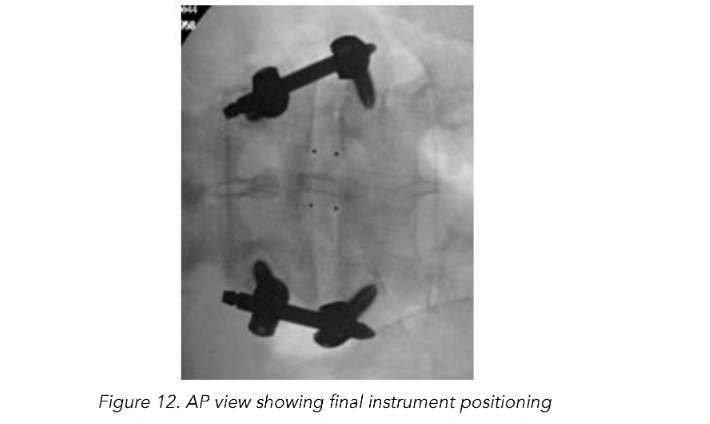

Once adequate decompression, interbody placement and complete hemostasis are achieved, the tubular retractor is removed, and an incision is made on the contralateral side, equidistant from the midline (3 cm), for the interbody fusion. AP and lateral fluoroscopy are used to target the pedicles for percutaneous pedicle screw fixation and place initial K-wires. Once the K-wires are placed they are then stimulated with concurrent neuromonitoring. A stimulation threshold less than 8 mAmps requires repositioning of K-wire or later pedicle screw. Percutaneous pedicle screws are placed bilaterally and segmentally to ensure suitable fixation to promote arthrodesis.

Total reduction of spondylolisthesis is performed by securing the rod to the most dorsal pedicle screw head (i.e., L5 seen in L4–5 spondylolisthesis) (Figure 10) and subsequently bringing the ventral pedicle screw head up towards the rod (Figure 11). This is done simultaneously bilaterally to reduce rotation and achieve total spondylolisthesis reduction thus restoring sagittal alignment. The advantages of this technique specifically arise from significant increases in the diameter of the neural foramen and spinal canal, and the larger surface area for fusion between adjacent vertebrae. The unique design of the PEEK Thompson MIS BoneBac TLIF device, with curved ends that correspond to the vertebral endplates, helps to facilitate reduction of the spondylolisthesis (Figures 10 and 11). Final tightening is performed, and the towers are removed allowing the paraspinous muscles to return to their normal anatomical position. Excellent long-term clinical outcomes and fusion rates using the MI-TLIF technique described have been achieved (Figures 13 and 14). More recently, but not within the patients covered in this data set, we began trialing augmented reality image guided navigation to place percutaneous pedicle screws in an effort to further reduce radiation exposure to both the patient and surgical team (Figure 15).